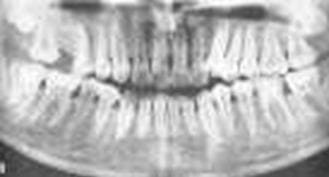

Это заболевание десен отличается от двух предыдущих иной природой возникновения. Гингивит и пародонтит – заболевания десен воспалительного характера, пародонтоз – дистрофического. Таким образом, и симптомы заболевания будут другими. При пародонтозе не встречается кровоточивости десен, их болезненности и отечности. Зубы хорошо фиксированы в костной ткани, зубных отложений нет или незначительны, шейки зубов оголены, может развиться «клиновидный дефект». Это приводит к повышенной чувствительности зубов к различным температурным и химическим раздражителям. Подвижность зубов развивается только при значительном разрушении костной ткани (более ½). И все-таки главным симптомом, по которому ставится диагноз и степень тяжести заболевания, является атрофия костной ткани. Этот симптом выявляется на рентгенограмме челюсти, правильно «прочитать» которую может только врач.

Фото Симптомы пародонтоза на рентгенограмме

Отсутствие расшатывания зубов, сохранение их прочного положения в лунке является отличительным симптомом пародонтоза.